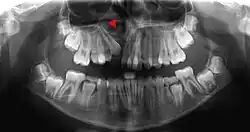

Pressure or pain in the jaw area can be associated with dilaceration. Checking in with a general dentist and an endodontist should be done if a patient feels these symptoms.[4] Signs in radiographic imaging will indicate a bend in the tooth's root as opposed to a straight growth.[1] Dilaceration of the crown, the top part of the teeth that we see when we smile, can be visually seen for diagnosis. Crown dilaceration will present itself as a tooth that is angled to face outward or inward. It will be a non axial displacement and more of a longitudinal displacement.[5]

Dilaceration can be diagnosed with a simple radiograph of the affected teeth. However, if the bends are more lingual or facially present,[1] more advance imaging techniques may be necessary. In some cases a cone-bean CT scan may be useful to create a three dimensional view.[9]